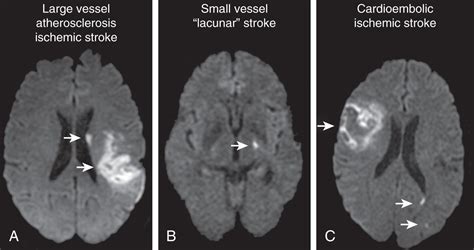

Differentiating Stroke Types

Another critical role of the CT scan is distinguishing between an ischemic stroke and a hemorrhagic stroke . A hemorrhagic stroke will show up as a bright area on the CT scan, indicating bleeding in the brain. For ischemic strokes, the scan will often initially appear normal or show the subtle signs mentioned above. This difference is super important because treatments vary dramatically. If the CT scan shows bleeding, clot-busting drugs are usually not an option. Instead, the focus is on controlling the bleeding and managing the pressure in the brain.

- MRI (Magnetic Resonance Imaging): An MRI can provide even more detailed images of the brain and may be used in cases where the CT scan is unclear or to assess the full extent of the damage. An MRI is better for detecting early changes in the brain tissue.